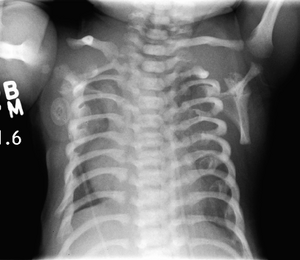

CXR of a newborn with asphyxiating thoracic dysplasia. Note the short ribs.

Asphyxiating thoracic dysplasia (ATD), also known as Jeune syndrome, is a rare inherited bone growth disorder (autosomal recessive skeletal dysplasia) [1]that primarily affects the thoracic region. It was first described in 1955 by the French pediatrician Mathis Jeune.[2] Common signs and symptoms can include a narrow chest, short ribs, shortened bones in the arms and legs, short stature, and extra fingers and toes (polydactyly). The restricted growth and expansion of the lungs caused by this disorder results in life-threatening breathing difficulties; occurring in 1 in every 100,000-130,000 live births in the United States.[3][4]

Anterior- indicates imbalance of shoulder/waist line, Lateral- thoracolumbar kyphosis

Jeune syndrome is a rare genetic disorder that affects the way a child’s cartilage and bones develop. It begins before the child is born and primarily affects the child's rib cage, pelvis, arms and legs.[6] Usually, problems with the rib cage cause the most serious health problems for children with Jeune syndrome. Their rib cages (thorax) are smaller and narrower than usual, which inhibits the child's lungs from developing fully or expanding when they inhale. The child may breathe rapidly and shallowly. They may have trouble breathing when they have an upper or lower respiratory infection, like pneumonia. Breathing trouble can range from mild to severe. In some children, it is not noticeable, aside from fast breathing; however, in others, breathing problems can be fatal. About 60% to 70% of children with this condition die from respiratory failure as babies or young children. Children with Jeune syndrome who survive often develop problems with their kidneys, and over time they may experience kidney failure.[2]